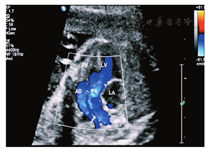

孕妇,27岁,孕1产0,孕25周。行产前超声检查示:胎儿如孕25+4周,腹部横切面显示腹主动脉与下腔静脉位置排列关系正常,腹腔脏器正位;四腔心切面显示心尖指向左侧,房室大小正常;心室流出道切面显示升主动脉(内径3.3 mm)及肺动脉大部分(内径6.7 mm)发自右心室,比例(PA/AO)为2.03,两者起始部呈平行排列,室间隔上部中断4.9 mm,肺动脉骑跨于室间隔上;彩色多普勒示左心室血流经过室间隔缺损直接射入肺动脉内(图1,图2);三血管及三血管气管切面显示主动脉位于肺动脉右前方,与动脉导管共同形成"V"形血管结构消失,多切面检查主动脉弓于左锁骨下动脉以下未能与降主动脉连续,无法显示完整的主动脉弓长轴切面(图3)。超声诊断:胎儿心脏发育异常,右心室双出口(Taussig-Bing型)、室间隔缺损、升主动脉发育不良、主动脉弓离断(A型)可能性大。胎儿引产后,心脏解剖证实超声诊断(图4)。